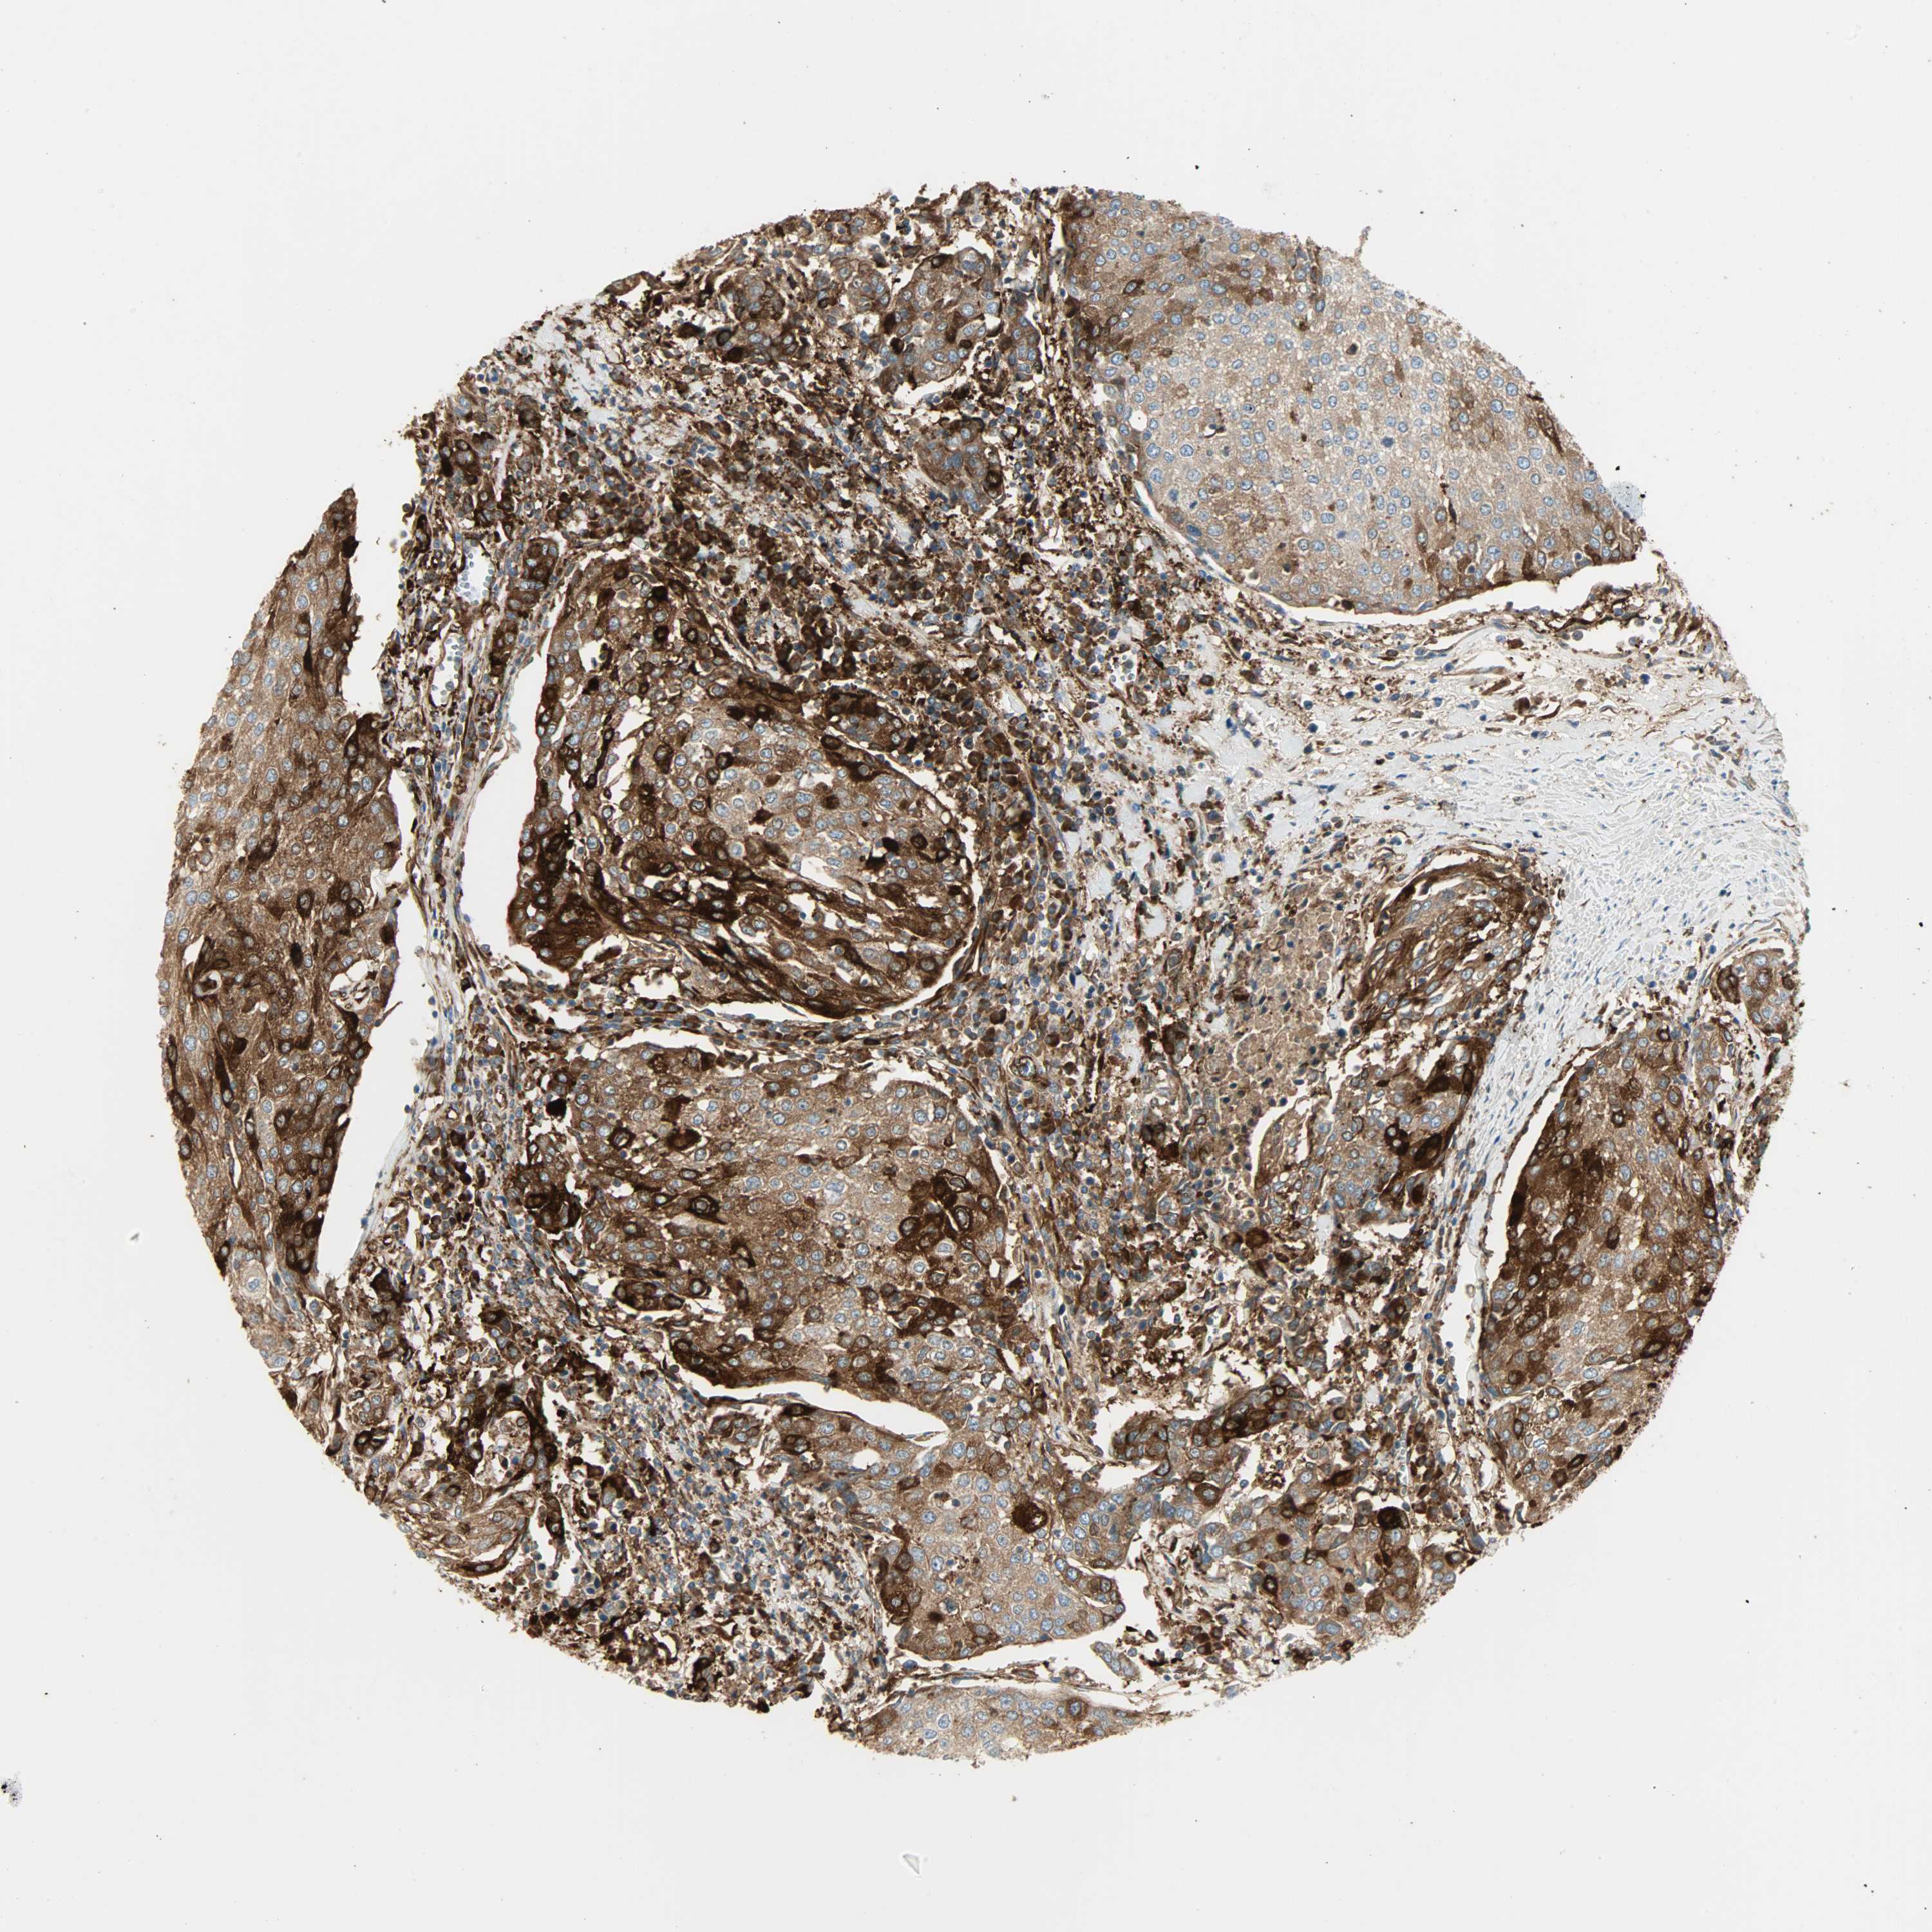

UROTHELIAL CANCER - Protein expressioni

A mouse-over function shows sample information and annotation data. Click on an image to view it in a full screen mode. Samples can be filtered based on level of antibody staining by selecting one or several of the following categories: high, medium, low and not detected. The assay and annotation is described here.

Note that samples used for immunohistochemistry by the Human Protein Atlas do not correspond to samples in the TCGA dataset.

Antibody stainingi

Antibody staining in the annotated cell types in the current human tissue is reported as not detected, low, medium, or high, based on conventional immunohistochemistry profiling in selected tissues. This score is based on the combination of the staining intensity and fraction of stained cells.

Each image is clickable and will lead to virtual microscopy that enables deeper exploration of all samples and also displays staining intensity scores, fraction scores and subcellular localization as well as patient and tissue information for each sample.

Antibody HPA005573

Staining

High

Medium

Low

Not detected

Intensity

Strong

Moderate

Weak

Negative

Quantity

>75%

75%-25%

<25%

None

Location

Nuclear

Cytoplasmic/membranous

Cytoplasmic/membranous,nuclear

Urothelial carcinoma, High grade

Urothelial carcinoma, Low grade